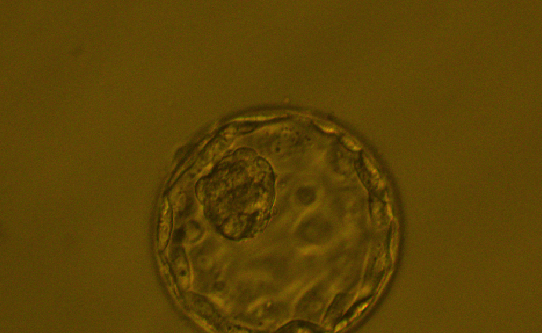

囊胚是胚胎发育过程中的一个阶段,类似小朋友长大过程中的某一必经阶段。对于胚胎移植一般选择体外发育到第3天或第5-6天的胚胎两种策略。我们把发育到第3天的胚胎称之为“卵裂期胚胎”,把发育到第5-6天的胚胎称之为“囊胚”。